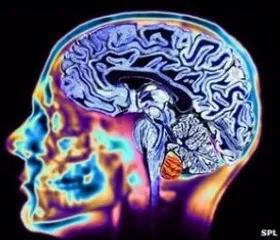

Children exposed to higher levels of air pollution in early and mid-childhood may have weaker connections between key brain regions that can highly impact their thinking and controlling capacity, according to a study.

New Delhi: Children exposed to higher levels of air pollution in early and mid-childhood may have weaker connections between key brain regions that can highly impact their thinking and controlling capacity, according to a study.

The research led by the Barcelona Institute for Global Health (ISGlobal) in Spain showed reduced functional connectivity within and between certain cortical and subcortical brain networks in kids with increased exposure to air pollution.

These networks are systems of interconnected brain structures that work together to perform different cognitive functions, such as thinking, perceiving, and controlling movement, said the team.

The results show that greater exposure to air pollution from birth to three years old is associated with lower connectivity between the amygdala and the cortical networks involved in attention, somatomotor function -- which coordinates body movements -- and auditory function.

Additionally, higher exposure to PM10 particles in the year before the neuroimaging assessment was associated with lower functional connectivity between the salience and medial-parietal networks -- responsible for detecting stimuli in the environment and for introspection and self-perception.